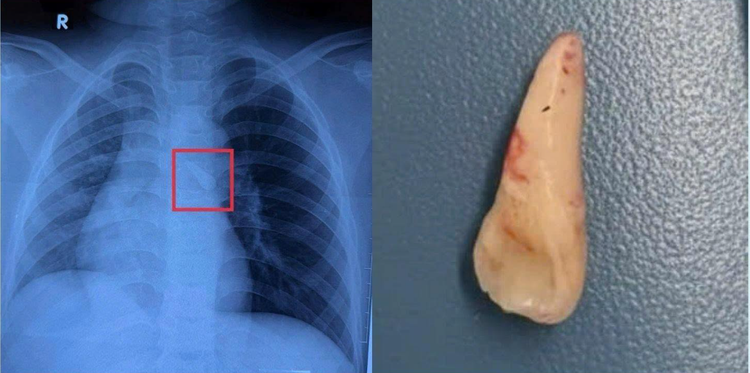

Qua nội soi, TS.BS Việt ghi nhận dị vật là một chiếc răng nằm trong carina của khí quản và đã gắp ra thành công. Sau phẫu thuật, đường thở của bệnh nhi thông thoáng, không ghi nhận chảy máu hay biến chứng. Trẻ tỉnh táo, hô hấp ổn định, ăn uống được và tiếp tục được theo dõi tại khoa.

di-vat.png

Chiếc răng nằm trong carina của khí quản và đã gắp ra thành công - Ảnh BVCC